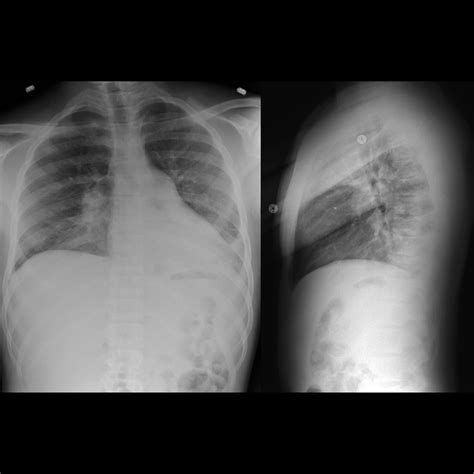

Acute Chest Syndrome is defined by the presence of a new pulmonary infiltrate on a chest X-ray, combined with clinical symptoms such as fever, cough, chest pain, sputum production, dyspnea, or hypoxia. While often triggered by a vaso-occlusive crisis or infection, the pathophysiology is multifactorial. In SCD, sickled red blood cells are rigid and misshapen, causing them to adhere to the endothelium and block blood flow, which leads to inflammation and injury within the lung tissue. This creates a feedback loop of worsening oxygen deficiency and further sickling, which necessitates immediate medical attention.

Once a patient is admitted, medical teams use a combination of diagnostics to confirm the diagnosis and assess severity. Standard procedures typically include pulse oximetry, chest radiography, and arterial blood gas analysis. Treatment is comprehensive and aggressive, focusing on reversing the sickling process and supporting respiratory function.